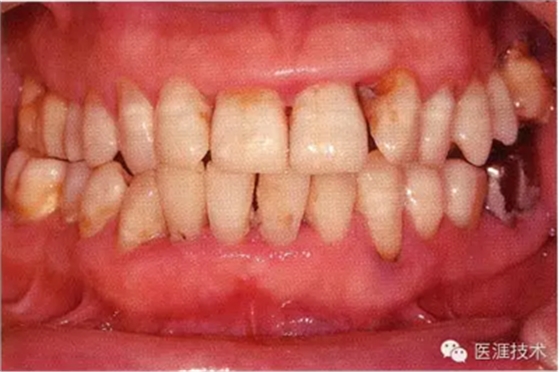

55歲牙周炎男性的臨床照片

55歲男性抽煙患者(1天20支、抽煙35年)。菌斑控制得不好。通過牙周探診,全頜有4~9mm的牙周袋,有1~3度的根分叉部病變。通過X光片觀察,上頜前牙中度牙槽骨吸收,其他地方有中度牙槽骨吸收。受吸煙影響,牙齦纖維性肥厚,呈紅黑色。牙齦幾乎沒有浮腫和發(fā)紅,所以這個(gè)病例是從外觀上無(wú)法預(yù)測(cè)病癥嚴(yán)重程度的病例。